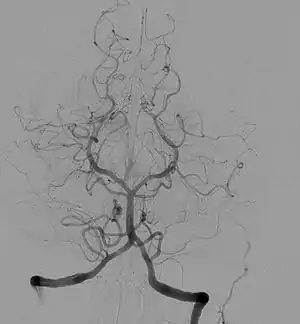

![]() Angiogram of the brain showing a transverse projection of the vertebro basilar and posterior cerebral circulation. | |

Cerebral angiography provides images of blood vessels in and around the brain to detect abnormalities, including arteriovenous malformations and aneurysms.[6] One common cerebral angiographic procedure is neuro-vascular digital subtraction angiography.[7][8]